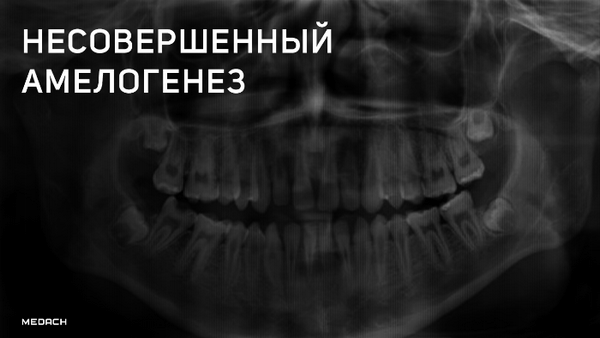

Лучевая диагностика несовершенного амелогенеза

Рентгенограмма при несовершенном амелогенезе